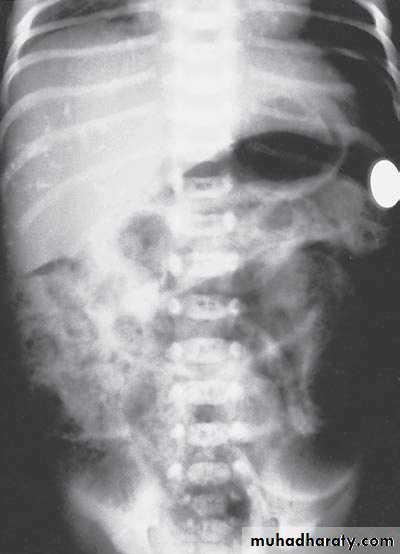

Bowel Obstruction

N.E.C

Meconium ileus+atresia

Hirschprungs disease